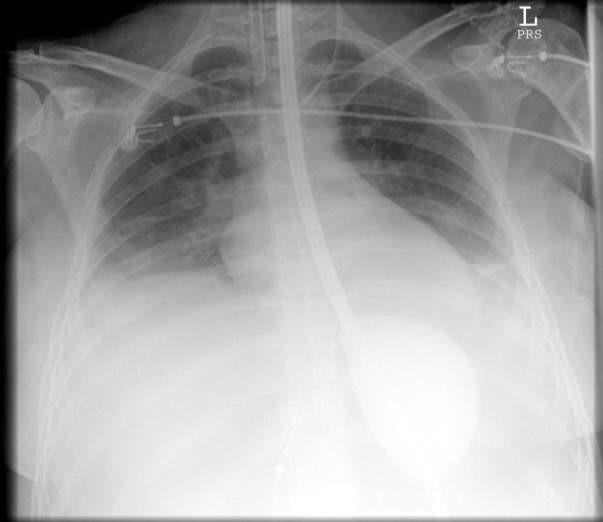

A critically ill 45 year old woman is intubated in the ICU. A procedure is performed and the following test is conducted

What was the procedure?